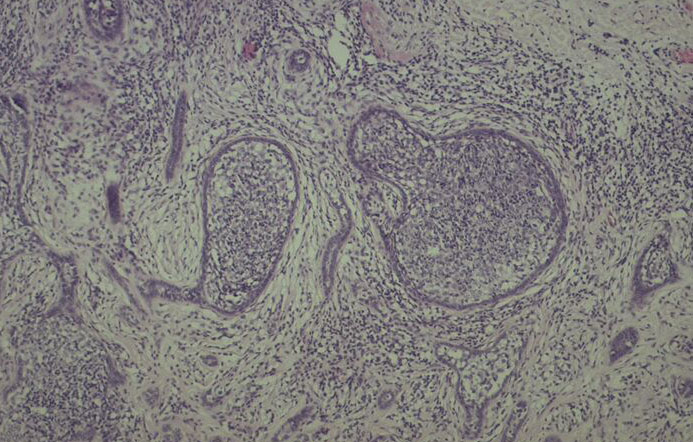

Cutaneous lymphadenoma =الغدوم اللمفاوي الجلدي